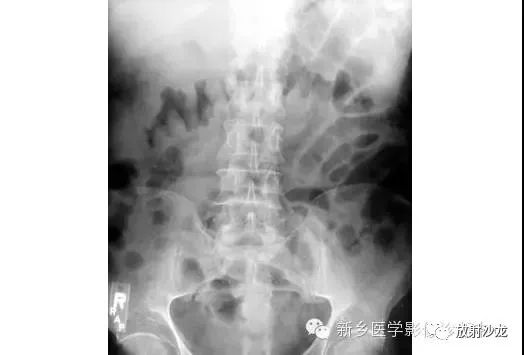

病例七:

上图为9岁,腹痛、呕吐患儿所做的腹部平片。该患儿有阑尾炎合并腹膜炎病史。影像学异常是什么,最有可能的病因是什么?腹部X线片显示小肠襻的明显扩张、环状襞的消失,这与小肠梗阻的诊断相一致。该患儿既往有腹膜炎病史,梗阻是由腹腔粘连造成的。这个孩子最终经保守治疗康复。